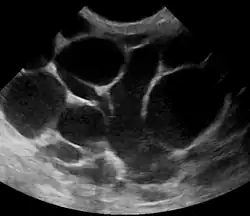

Risk factors include poor latch, cracked nipples, and weaning.[1] Use of a breast pump has historically been associated with mastitis, but has been determined as an indirect association.[7] The bacteria most commonly involved are Staphylococcus and Streptococci.[1] Diagnosis is typically based on symptoms.[2] Ultrasound may be useful for detecting a potential abscess.[1]

The diagnosis of mastitis and breast abscess can usually be made based on a physical examination.[24] The doctor will also take into account the signs and symptoms of the condition.

However, if the doctor is not sure whether the mass is an abscess or a tumor, a breast ultrasound may be performed. The ultrasound provides a clear image of the breast tissue and may be helpful in distinguishing between simple mastitis and abscess or in diagnosing an abscess deep in the breast. The test consists of placing an ultrasound probe over the breast.